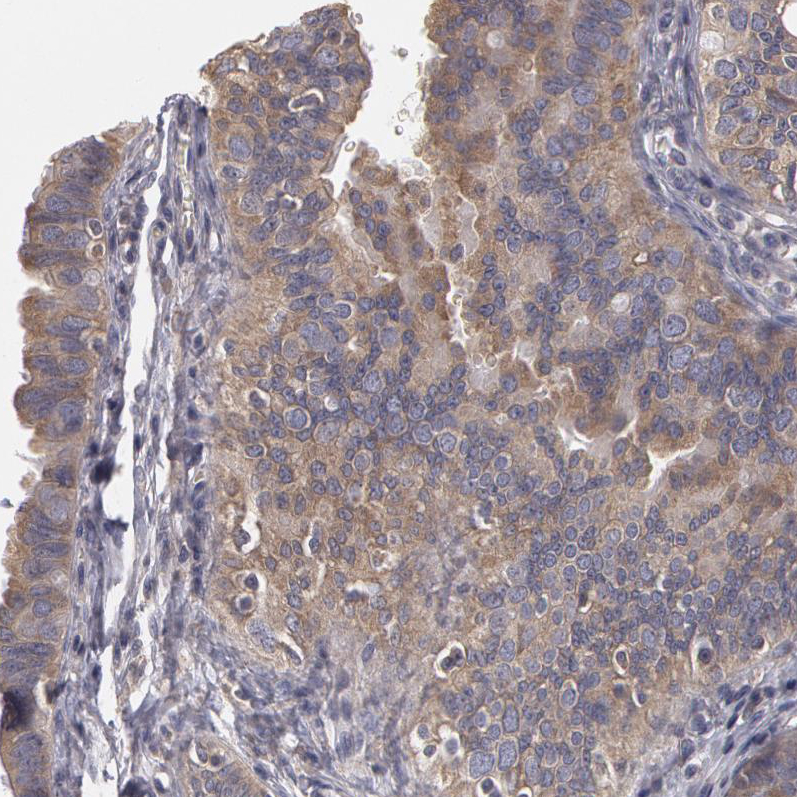

Immunohistochemical staining of human fallopian tube shows weak to moderate cytoplasmic positivity in glandular cells.